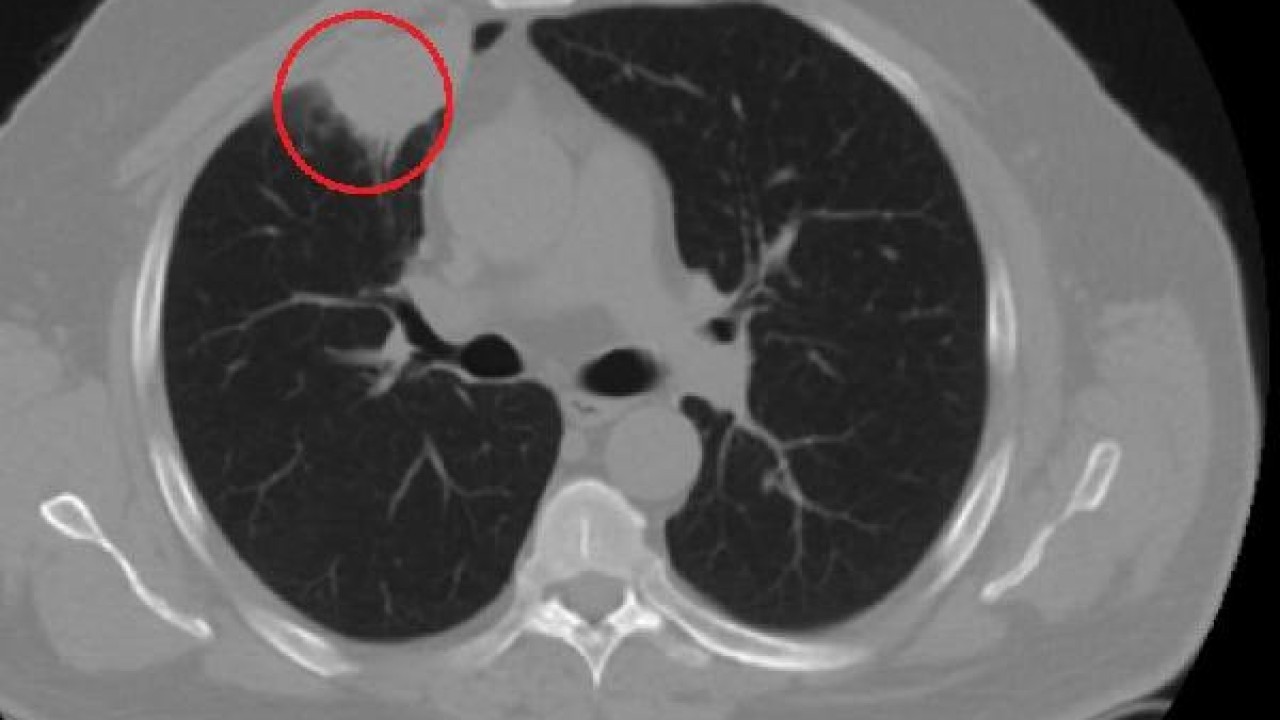

"Hastamız, çalıştığı başka bir kentte göğsünden darbe alıyor ve ağrıları geçmeyince bir üniversite hastanesine başvuruyor. Burada hastaya bir akciğer grafisi çekiliyor. Sağ akciğerinde bir kitleye rastlanıyor. Daha sonra hastaya, bir akciğer tomografisi çekiliyor ve göğüs cerrahisi için önemli büyüklükte olan 4 santimetre çapında, akciğer kanserine benzer özellikte radyolojik bulgular olan bir kitle tespit ediliyor. Daha sonra hastaya yapılan ileri tetkiklerde akciğer kanseri teşhisi konuluyor. Hastaya bir cerrahi planlanıyor. Hasta Kahramanmaraşlı olduğu için kendi memleketine gelmeyi tercih ediyor. Bize başvurdu ve göğüs ağrısı şikayeti vardı. Öksürük, nefes darlığı, balgam çıkarma, ateş gibi şikayetleri yoktu. Hastayı biz de değerlendirdik ve ameliyat olmasına karar verdik. Çünkü akciğer kanserine çok benzer radyolojik bulguları vardı. Sağlık Bakanlığımızın kuralları gereği her hastayı ameliyat öncesi PCR testi yapılır. Biz de ameliyat gecesi hastadan PCR testi aldık ve testi pozitif geldi. Ameliyatımızı 14 gün erteledik ve hastamıza koronavirüs tedavisi uygulandı. Hasta 14'üncü gün tekrar bize başvurdu ve yapılan PCR testi negatif çıktı. Yeni bir tomografi çektik ve tümörün tamamen ortadan kalktığını gördük. Şimdi sonuç bilgilerinden başlangıca gittiğimizde, bu bir akciğer kanseri olsaydı, ortadan kalkması mümkün değildi. Başka bir patolojiye bağlı durum olsaydı, yine verdiğimiz tedaviyle ortadan kalkmasını çok beklemeyiz. Antiviral tedavisi verdik ve hastanın radyolojik bulguları neredeyse tamamen normale döndü. Hastaya bunu izah ettik, 'Dünya literatüründe hiç görülmeyen bir radyolojik bulgu' diyerek. Bu gördüğümüz manzara artık hastanın akciğer grafisinde yok, akciğer kanseri değil. "

Hastayı takip etmeye devam ettiklerini belirten Kozanlı, 2 yıldır dünyayı etkisi altına alan koronavirüsün akciğer kanserini taklit ettiğini, böyle bir durumla ilk defa karşılaştıklarını söyledi. Hem Türkiye'de hem de diğer ülkelerde buna benzer bir vakanın olup olmadığını araştırdığını ifade eden Kozanlı, "Genel olarak dünya literatürüne baktığımızda koronavirüsün akciğer bulguları, radyolojik bulguları infiltrasyon, buzlu cam dansitesi gibi bilinen bulgular. Ama bizim hastamızda akciğer tümörünü taklit eden bir kitle vardı. Ve biz bunu dünya literatüründe hiç görmemiştik. Bununla ilgili geniş çaplı bir araştırma yaptım. Hem kendi deneyimlerimden hem kendi hastanemizde yatan hastalardan yola çıkarak birçok hastanın radyolojik bulgularına baktık. Dünya literatürlerini karıştırdım, diğer arkadaşlarıma danıştım, benzeri bulguya rastlamadım" diye konuştu.